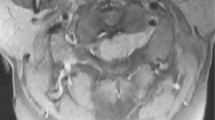

The epidural presentation in eight patients was heralded by motor signs (paraparesis and plegia), in one by a lesion of the posterior columns of the spinal cord (ataxia), and in three by pain. One patient was free of complaints and symptoms. The affected epidural area was diagnosed previously by myelography and computerized tomography (CT), and later by magnetic resonance (MR), over the course of which the location was verified as thoracic in eight patients, cervical in one, and lumbar in four. The authors recommended surgical intervention in 9 out of 13 cases, in seven cases of Hodgkin's and six cases of non-Hodgkin's lymphoma. Seven patients were treated for recognized manifestations of malignant lymphoma while six were diagnosed by intraoperative-histological examination.

The decompression operations for tumors resulted in limited improvement in seven patients (reduction in pain and return of ability to walk). Four patients were not operated on, two of which had significant improvement in their neurological symptoms. Paraparesis remained unchanged in one patient. One patient remained symptom-free. The authors emphasize the importance of interdisciplinary consultation and weighing individual priorities in the indications for operation on epidural ML.